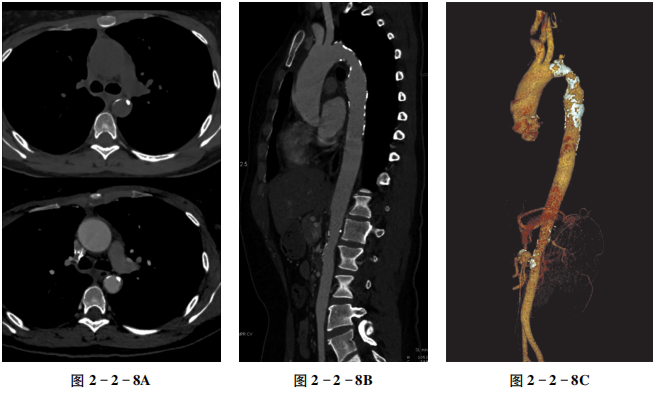

例8

大动脉炎

女性,35岁。反复头晕1个月余。

【CT征象】

CT横断面图像示升主动脉管壁较均匀增厚(图2-2-8A);曲面重组、容积再现图像示主动脉粗细欠均匀,局部管腔较狭窄,管壁可见钙化(图2-2-8 B、C)。

【重要征象】

血管壁环形增厚,管壁钙化,管腔向心性轻度狭窄。

【CT拟诊】

①大动脉炎。②动脉粥样硬化。③结节性多动脉炎。④巨细胞动脉炎。

【最终诊断】

大动脉炎。

【评述】

大动脉炎,又称“无脉病”,是一种发生于大弹力动脉的慢性非特异性炎性疾病。好发于20~30岁年轻女性。病理改变主要以T淋巴细胞、B淋巴细胞和巨噬细胞浸润为主的透壁性血管炎。受累动脉外膜呈结节样增厚,中膜和内膜增生、纤维化,致管腔狭窄甚至闭塞;也可见管腔扩张、动脉瘤和(或)血栓形成。

病变分为5型:I型,累及主动脉弓主要分支血管;Ⅱa型,累及升主动脉、主动脉弓及其主要分支;Ⅱb型,累及升主动脉、主动脉弓及其主要分支和胸主动脉;Ⅲ型,累及胸主动脉降段、腹主动脉和(或)肾动脉;IV型,仅累及腹主动脉和(或)肾动脉;V型,Ⅱb型+IV型。在上述分型的基础上,冠状动脉受累时为C+,肺动脉受累时为P+。

CT表现

①血管壁环形增厚为最典型表现,也是该病早期主要表现,CT平扫上环形增厚的血管壁相对于管腔呈略高密度,增强扫描时增厚的管壁可出现“双环征”。②血管腔狭窄或闭塞:为向心性狭窄,见于90%的患者,以胸主动脉降段和腹主动脉受累常见,最常受累分支血管为左锁骨下动脉、颈总动脉和肾动脉,肺动脉和冠状动脉也可受累。③管壁钙化:以透壁性钙化为典型表现,可见于27%的患者。④管腔扩张或动脉瘤形成:以腹主动脉和升主动脉最常见。⑤侧支循环血管:表现为狭窄或闭塞血管周围大量迂曲、增粗的小血管。

鉴别诊断

大动脉炎诊断要点为年轻女性,多发大动脉受累,管壁环形增厚伴管腔向心性狭窄或闭塞,可伴侧支循环形成。注意与以下疾病鉴别:①巨细胞动脉炎:受累部位主要位于颈外动脉及其分支和颈内动脉,且常见于50岁以上女性。②结节性多动脉炎:好发于30~50岁男性,受累部位主要位于内脏动脉如肾动脉,以多发小动脉瘤样改变为特征。③动脉粥样硬化:管壁不均匀增厚,钙化常见,管腔偏心性狭窄,以40岁以上患者多见。